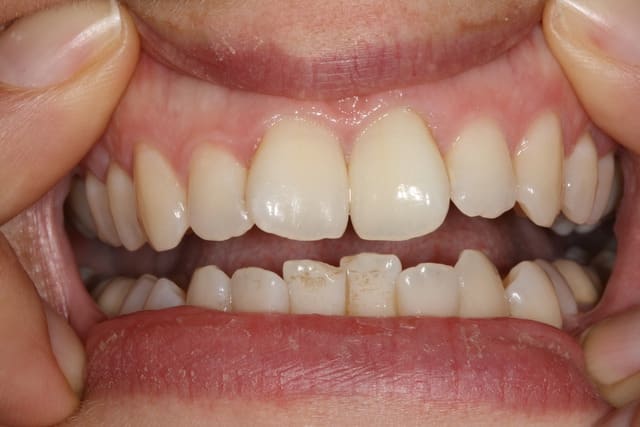

C'est un blanchiment interne comme si l'endo était faite (après recherche effrénée d'un hypothétique canal), et après contrôle +++ d'une isolation +++ . La patiente n'a aucun souvenir d'un traumatisme sur cette dent .

donc j'avais bien raison tu as fait un blanchiment interne sans avoir pu faire l'endo a cause du canal calcifié?

Si on décide d'être le moins invasif , j'ai jugé raisonnable de tenter quand même malgré l'impossibilité de repérage de l'entrée du canal . Faire une facette c'est passer un cap , et je n'ai de prothésiste capable de reproduire les stries visibles sur la photo de départ de tout façon donc je n'ai compté que sur moi même .

Merci du cas , ça m'intéresse car j' ai vu plusieurs patientes dans ce cas avec canal totalement calcifié invisible à la radio mais je n' aurais jamais osé faire un éclaircissement interne car les dents sont vivantes même si leur réponse aux stimuli est atténuée. Combien as- tu de recul? Pas de nécrose par la suite? J' avais tenté un éclaircissement externe mais cela a très mal marché malgré trois séances. Dans deux cas je pense que la calcification est dûe à un trauma occlusal, dans le troisième que j'ai pu voir il s' agit peut-être de forces ortho excessives. Les trois cas que j' ai en tête, car il y a un moment que je ne les ai pas vues, concernaient exclusivement des femmes, mais peut être qu' elles ont plus tendance à consulter que les hommes pour ce motif, par coquetterie.